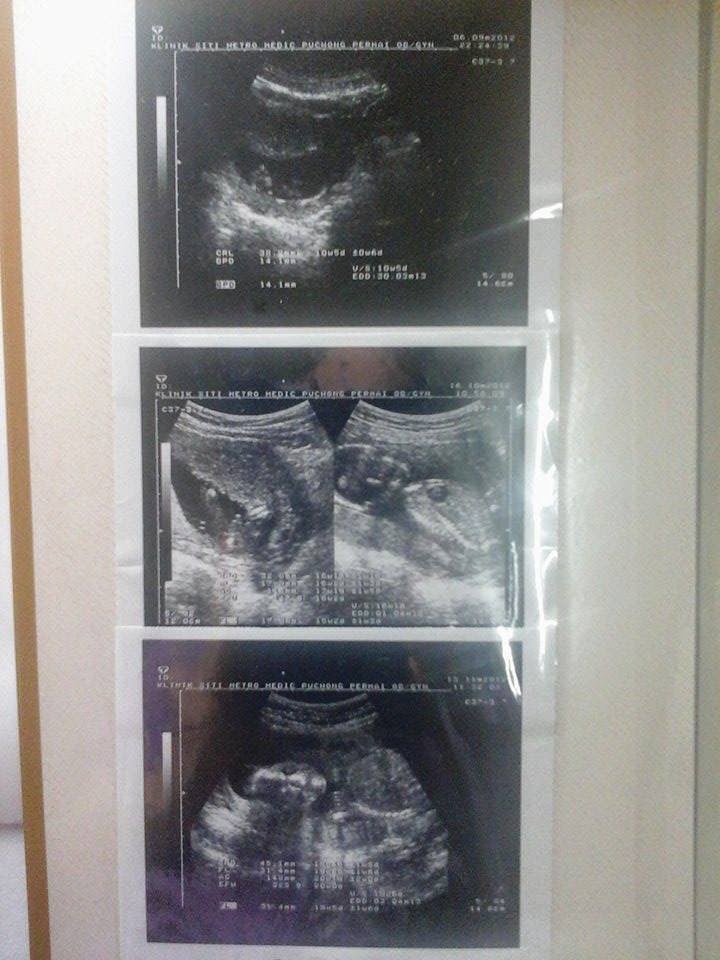

Seperti biasa diawal kehamilan aktiviti muntah memuntahkan, tidur ketiduran.. hehe.. oleh sebab simtom sama cam anak sulong, wani ingat anak kedua ni pompuan jugak.. tak kisah la ramai anak dara leh tolong mak masak..kann.. wani scan baby setiap bulan sbb dlu wani penah ada keguguran sbb baby tak berkembang.. Alhamdulillah baby ni berkembang mekar dalam rahim..